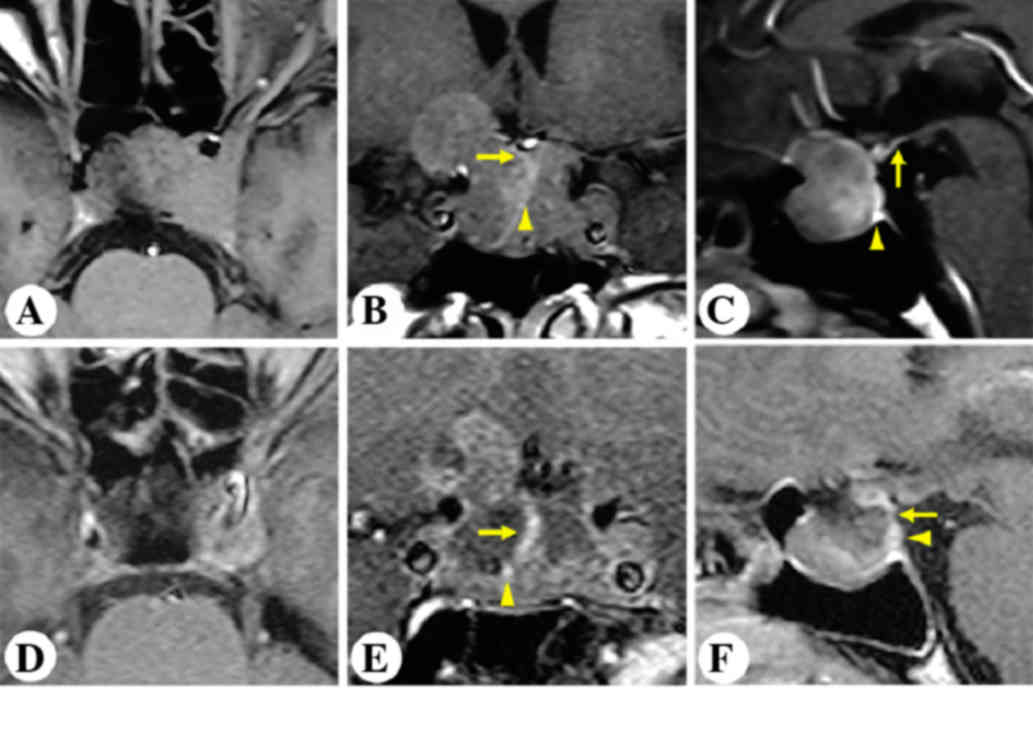

Case 2

A 48-year-old female complained of progressive intermittent headache and dizziness for the past nine years. MRI revealed an intrasellar and suprasellar non-enhancing lesion, invading the left cavernous sinus and the sphenoidal sinus. The stalk was displaced posterolaterally to the right (Fig. 3A-C). The patient underwent microscopic transphenoidal surgery. Postoperative MRI outlined GTR of the tumor and an anatomically intact gland and stalk (Fig. 3D-F).

Figure 3.

Patient 2. Representative post contrast T1-weighted images. Preoperative (A) horizontal, (B) coronal and (C) sagittal and postoperative (D) horizontal, (E) coronal and (F) sagittal magnetic resonance imaging of the sellar region. Arrows indicate the pituitary stalk. Arrowheads indicate the pituitary gland.